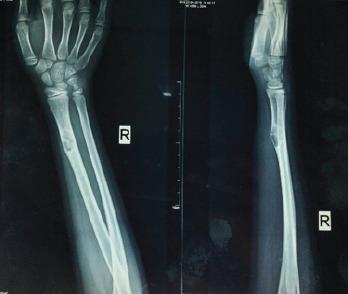

An 11-year-old skeletally immature girl presented to us two 2 years back with pain and swelling over the right forearm without any restriction of moments and other constitutional symptoms. She was diagnosed to have non-ossifying fibroma and had underwent surgery for the same 4years back. Radiographic and higher imaging studies suggested non-ossifying fibroma. Since the lesion was painful and the child had difficulty in carrying heavy objects, we decided to intervene. Tumour tissue was thoroughly curetted and the defect was filled with artificial bone substitute. Biopsy confirmed the diagnosis of non-ossifying fibroma and post-operative radiograph showed some residual tumour which was noted even at one 1-year follow-up X-ray. On 3-years follow-up,the patient was symptom-free with no residual lesion and complete incorporation of the artificial bone substitute.

一名11岁骨骼未成熟的女孩两年前前来就诊,右前臂疼痛肿胀,无任何活动受限及其他全身症状。她被诊断为非骨化性纤维瘤,4年前曾为此接受手术。放射学及更高分辨率影像学检查提示为非骨化性纤维瘤。由于病变疼痛且患儿搬运重物困难,我们决定进行干预。彻底刮除肿瘤组织,并用人工骨替代物填充缺损。活检证实为非骨化性纤维瘤,术后放射照片显示有一些残留肿瘤,甚至在1年随访X线检查时仍可见。在3年随访时,患者无症状,无残留病变,人工骨替代物完全融合。